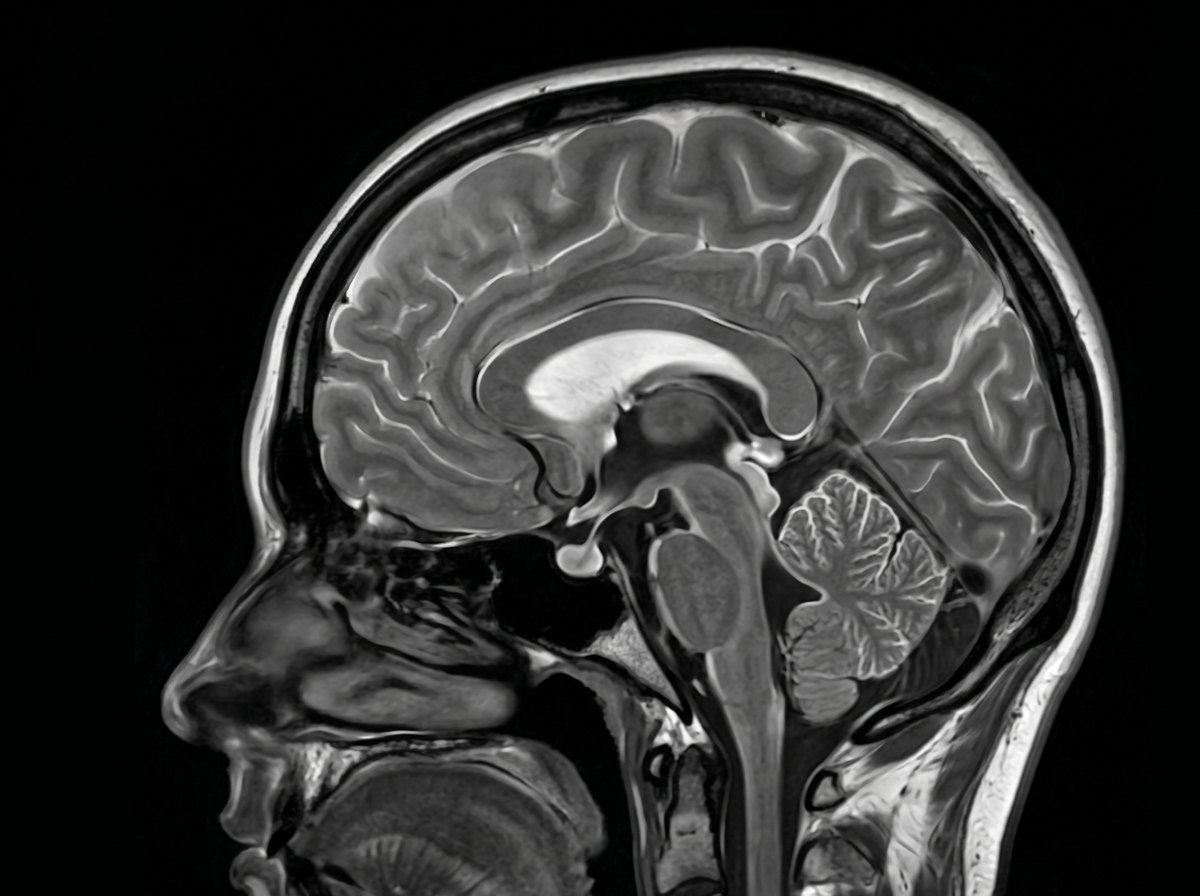

Sagittal T2-weighted MRI — illustrative reference only, not an AEVUM patient scan

SAGITTAL · T2W 3.0T · 0.7mm slice

SIEMENS MAGNETOM VIDA SE-1287 · 04/26

ModalityMRI · 3.0 Tesla

Coverage (Comprehensive)Head → Pelvis

Slice resolution≤ 1.0 mm

Reading radiologistConsultant on duty

Report turnaroundSame day